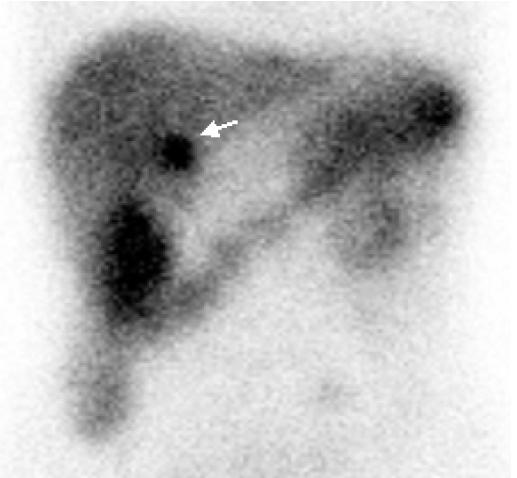

Figure 3.

Somatostatin receptor scintigraphy. Hot uptake lesion consistent with CT scan are noted around the pancreatic head.

장기간의 설사를 동반한 복통, 재발성의 소화성 궤양 및 식도 협착 등을 근거로 가스트린종에 대한 확진을 위하여 시행한 공복시 혈중 가스트린은 1,263 pg/mL으로(정상치 90 pg/mL) 증가되어 있었고, 복부 전산화단층촬영에서 십이지장 제2부와 췌장 두부의 경계부 그리고 췌장 미부에 각각 1.4 cm와 0.8 cm의 결절들이 관찰되었다(그림 2). 정확한 진단 및 병소 파악을 위하여 somatostatin receptor scan (SRS)을 시행하였다. 소마토스타틴 유사체인 옥트레오타이드에 111Indium을 표지자로 사용하여 4 mCi를 정주하였고, 주입 후 4시간 및 24시간 경과 후의 영상을 얻었다. SRS를 전산화단층촬영의 영상과 비교하였을 때 전산화단층촬영에서 관찰되던 췌장 두부 경계부 병변은 열결절로 나타났으나, 췌장 미부의 병변은 뚜렷이 관찰되지 않았다(그림 3). 가스트린종과 동반될 수 있는 다발성 내분비 종양 제 1형을 배제하기 위해 시행한 혈액검사에서 혈청 칼슘 10.2 mg/dL, 부갑상선 호르몬 66.5 pg/mL로 약간 증가되어 있었으며, 경부 초음파검사에서 왼쪽 갑상선 기저부에 약 0.6 cm의 결절이 관찰되어 부갑상선종이 의심되었다. 부갑상선 병변을 확인하기 위해 부갑상선 스캔(99 mTc MIBI 20 mCi)을 실시하였고, 초음파 소견과 일치되는 부위에 열결절이 관찰되었다(그림 4). 뇌하수체 병변을 검사하기 위해 자기공명영상을 실시하였으나 병변은 관찰되지 않았다.